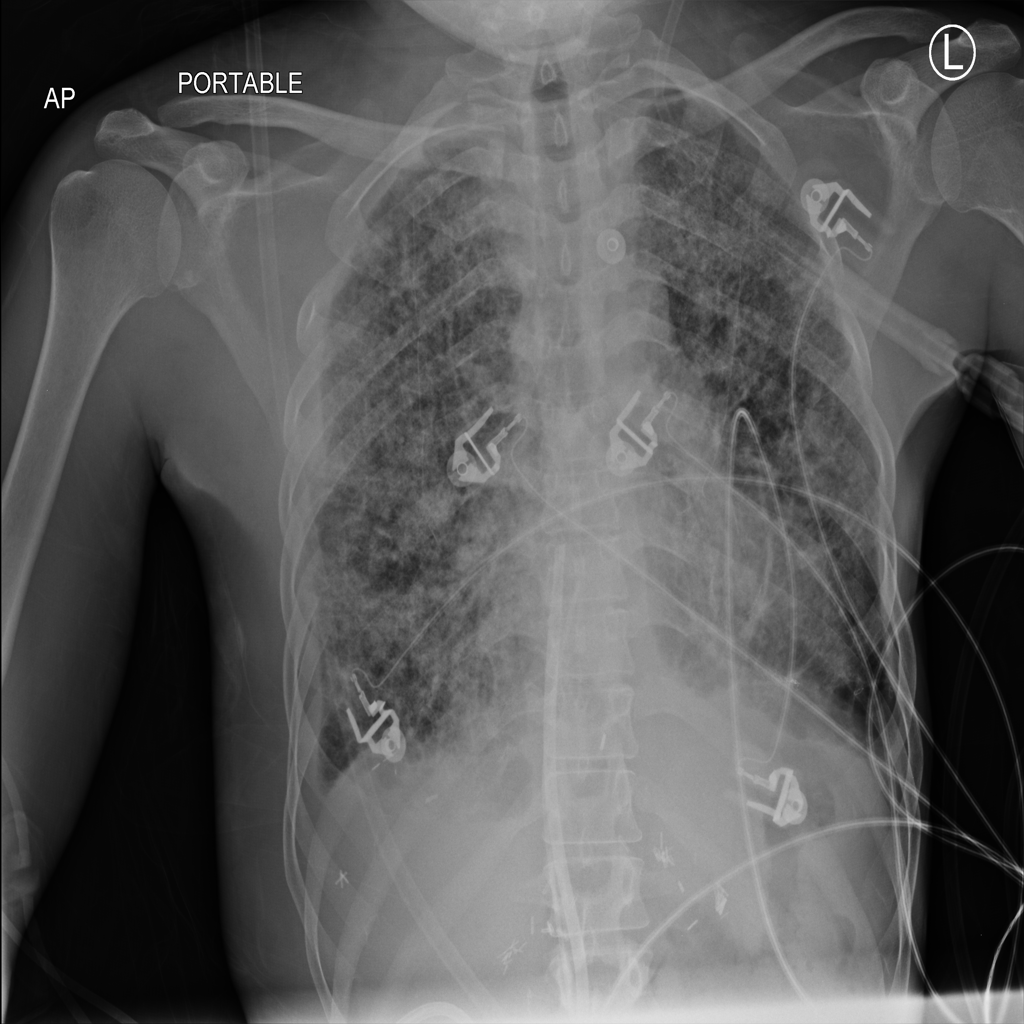

Pleural Effusion

Pleural effusion means extra fluid has collected around the lung in the pleural space. It can happen with heart problems, infection, inflammation, or other underlying conditions.

Showing up to 90 reference images for Effusion.

PAT-E81B · IMG-000Effusion

PAT-E81B · IMG-000

PA